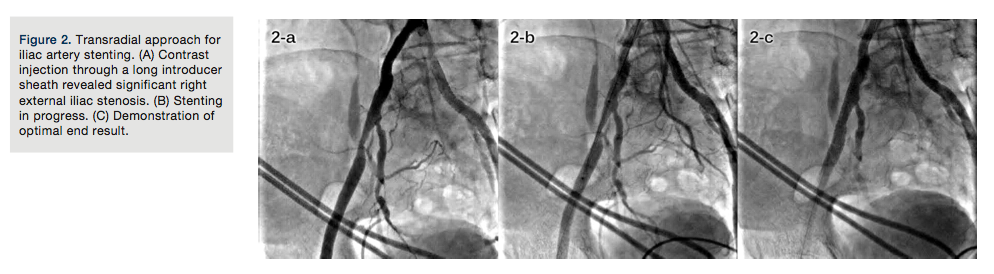

TRA for subclavian and innominate artery stenting. Occlusive lesions of the innominate and subclavian arteries might cause serious morbidity and should be treated if symptomatic. Endovascular treatment is recommended because it has a lower complication rate compared with surgical methods.46-48 Most studies have used the femoral approach; however, some have used brachial and axillary approaches.46,47 Ipsilateral TRA is a feasible and reproducible approach (Figures 3A, 3B, and 3C).

45cm-long, 6Fr or 7Fr introducer sheaths should be used for ipsilateral TRA, and the distal tip should be kept near the lesion.

While addressing innominate artery stenosis, care should be exercised in placing the stent, so that it does not protrude much into the aorta or into the orifice of the right common carotid artery.